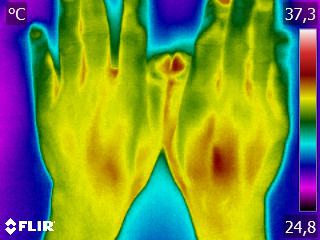

Grâce à la récente évolution des performances informatiques, la thermographie (ou imagerie thermique) nous permet aujourd’hui de voir, photographier et mesurer ces variations de température avec une extrême précision, de déceler des anomalies autrement invisibles, et d’en analyser les résultats. Par exemple, une zone hyperthermique (chaude) indiquera une inflammation, alors qu’une zone hypothermique (froide) révélera une tuméfaction, une détérioration nerveuse ou un tissu cicatriciel.

La thermographie nous oriente sur la source réelle, parfois cachée, du problème: non pas par déduction en fonction des symptômes, mais par visualisation directe. Elle ne se substitue pas aux autres techniques de diagnostic, mais tient une place privilégiée dans ce domaine puisqu’elle permet d’identifier d’éventuels problèmes avec une méthode différente, non-invasive, pertinente, précise et particulièrement précoce, ce qui en fait un outil de premier choix dans le monde médical, le domaine du diagnostic – et pour la santé en général.

La thermographie est capable de donner une image claire de n’importe quelle partie d’un être vivant, et ses domaines d’application sont aussi vastes qu’il existe de soucis, douleurs et maladies !

Les images parlant souvent mieux que les mots, voici quelques exemples concrets:

| Ventre | Dos | Articulations |

Ces quelques exemples soulignent encore une fois l’importance de la prise en charge d’une personne et de son corps dans sa globalité.